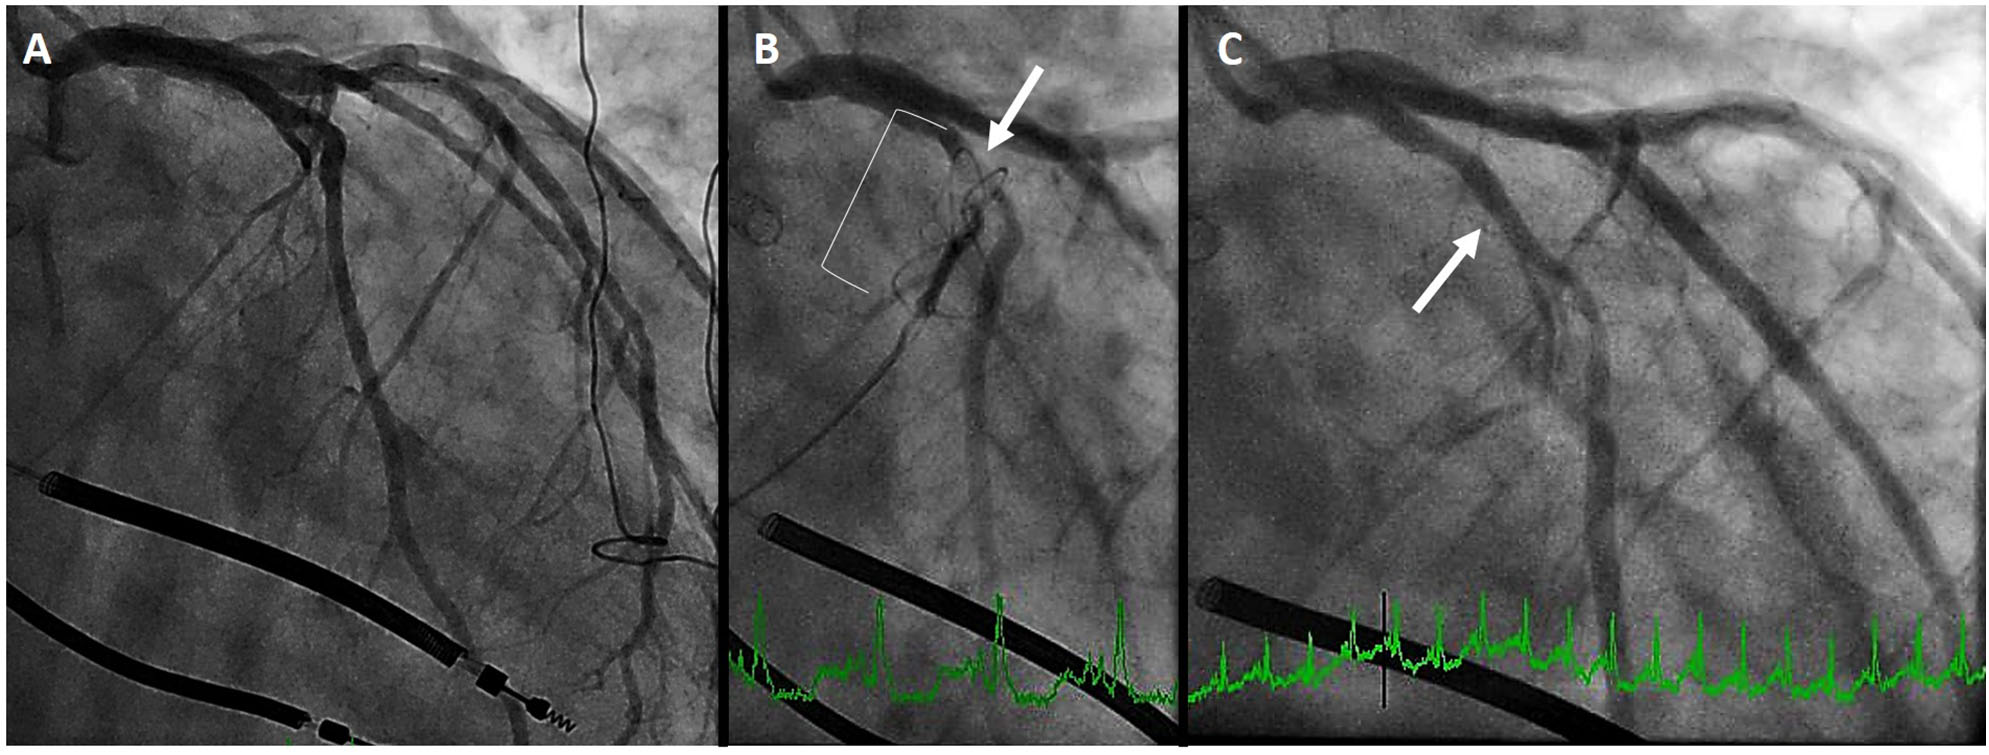

In the aforementioned analysis of cardiac CT, Choure et al. demonstrated that the LCx coronary artery crosses between the CS and MVA in 80% of patients. While the location of this crossing is variable, allowing CS annuloplasty in a great number of patients, it is important to be cognizant of this complication. Among the three initial trials of the Carillon previously discussed, coronary compression precluded device placement in 10–15% of patients. In REDUCE-FMR, eight patients of the 87 (9%) planned for a device could not receive one due to coronary compression (which resolved in all with device recapture). Figure 4 demonstrates a patient in whom the proximal circumflex was compressed by the distal anchor. As is common, the compression was relieved by recapture of the device.

Figure 4

Left circumflex coronary artery compression. (A) initial coronary angiogram. (B) distal anchor (bracket) causing compression of the proximal circumflex (arrow) (C) angiography after recapture of the Carillon demonstrates resolution of circumflex compression (arrow).